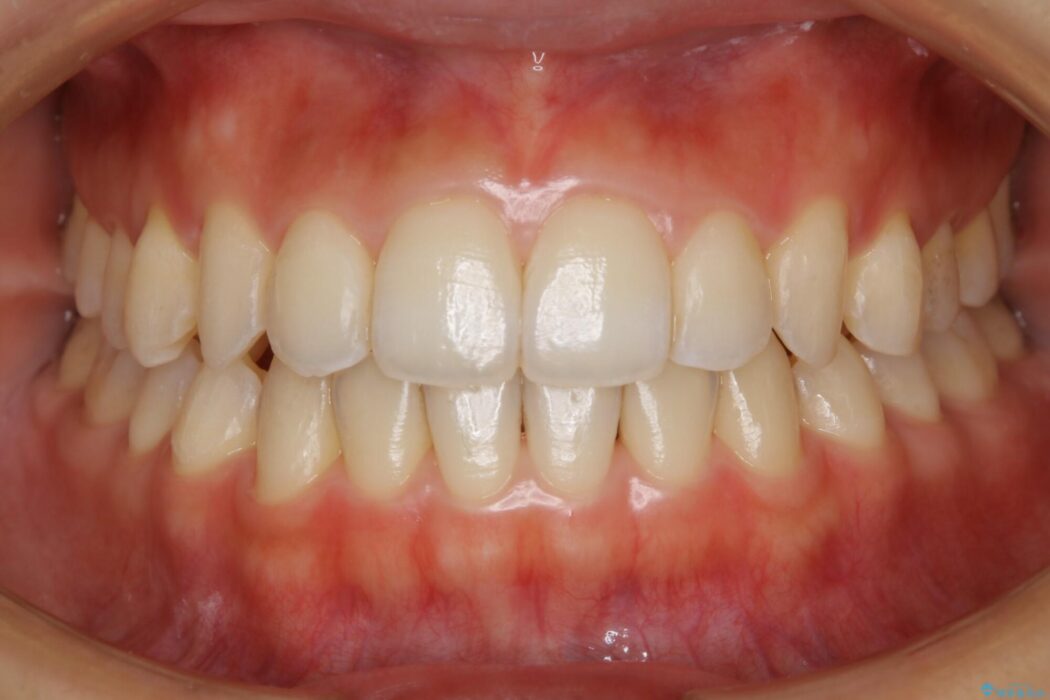

治療後写真を見ても歪みが解消され、歯列弓がきれいに整ったのが分かると思います。インビザラインをしっかりと装着されていたこともあり、矯正としては短期間の治療となりました。